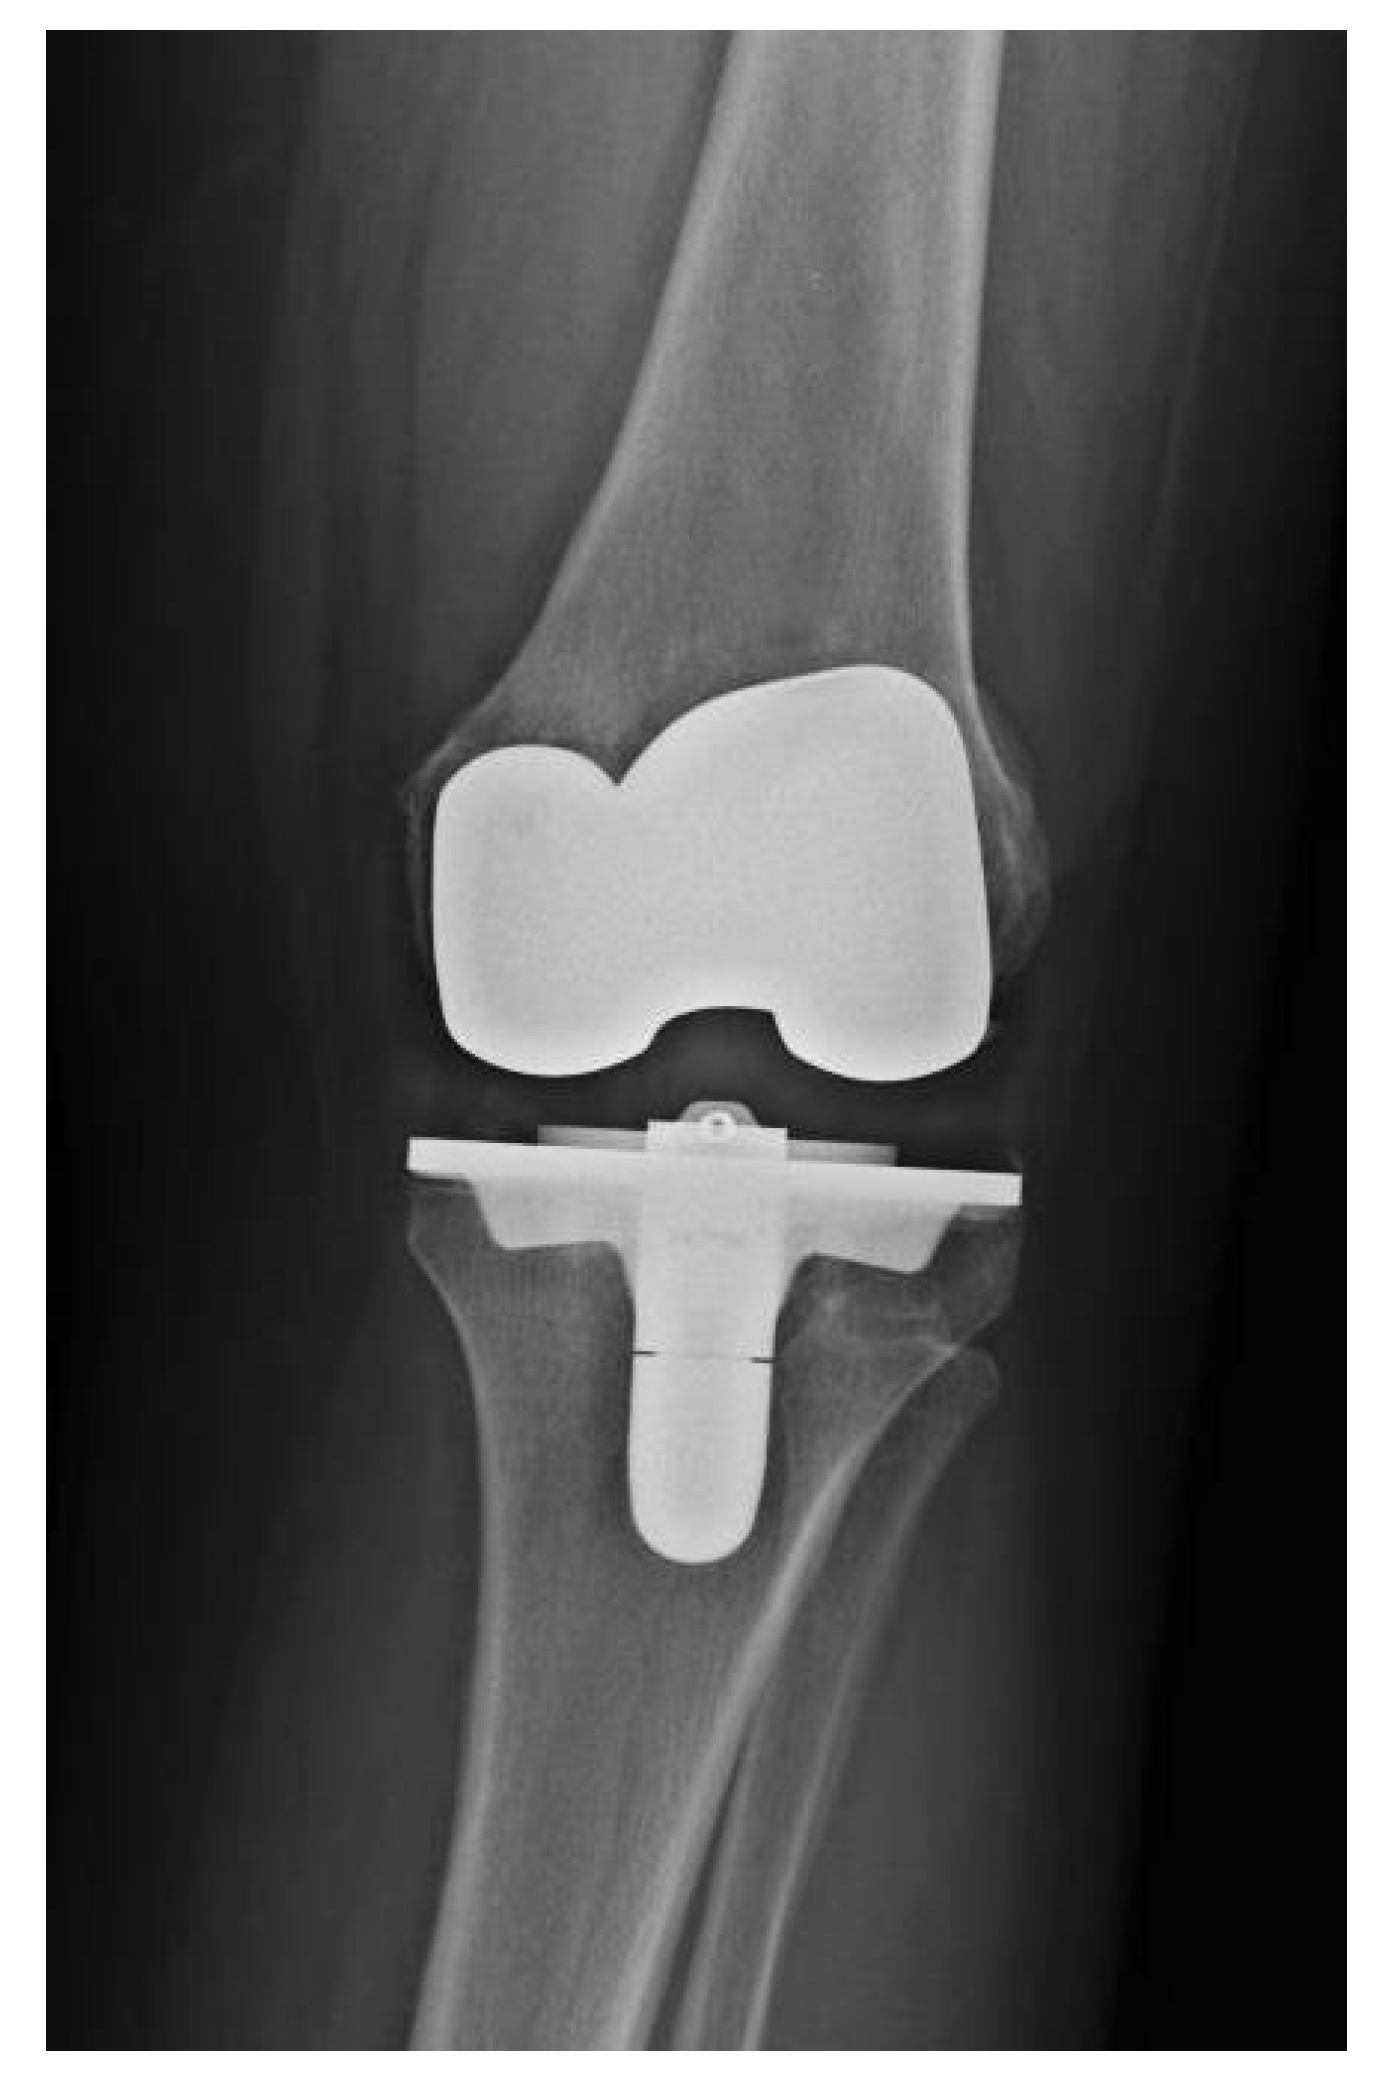

The surgery was split into two parts. The patient was placed in a supine position, and removal was always performed through pre-existing incisions. Meticulous surgical debridement was performed, and the wound was washed out with 9 L of normal saline. This was the end of the first part of the operation, and the patient was redraped and new instruments were used. The surgical team rescrubbed and put on new gowns. In all cases, implantation of a new arthroplasty was performed. Reconstruction of the joint was carried out with implantation of a cemented knee implant (eight cases of Endo-Model® Rotating Hinge Prosthesis Link® (Hamburg, Germany), one case of Megasystem-C Revision System Link® (Hamburg, Germany), eight cases of Legion RK Revision Knee Replacement Smith&Nephew® (Hertfordshire, United Kingdom), one case of Legion HK Hinge Knee Replacement Smith&Nephew® (Hertfordshire, United Kingdom), and one case of P.F.C.® Sigma® TC3™ DepuySynthes® (Warsaw, IN, USA). Antibiotic-loaded (gentamicin or gentamicin plus vancomycin) polymethylmethacrylate (PMMA) bone cement was used for both the fixation of the new implant and reconstruction of bone defects. The surgical team used premixed antibiotic bone cement and we never added any other antibiotics into the cement.